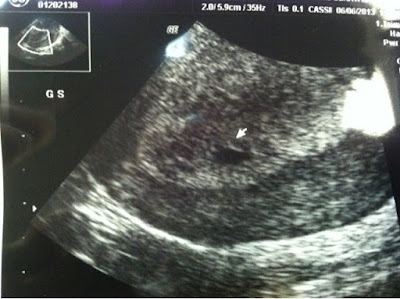

And here is the one from 5 weeks 6 days:

In case you're not familiar with ultrasounds, in the first one what you see is the gestational sac. In the second picture, you can see both the yolk sac and gestational sac. Cool right?